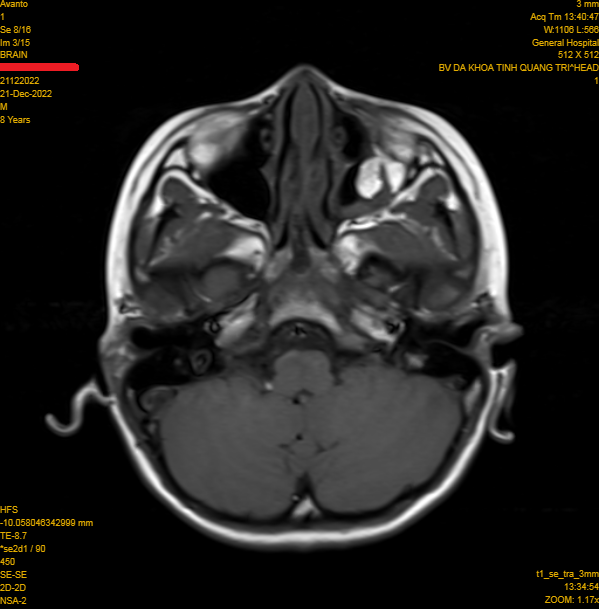

Chụp X-quang và CTScan hốc mắt thấy rõ vùng xương hốc mắt bị tổn thương. Chụp CTScan/MRI có thể cho thấy cơ bị xoắn hoặc kẹt vào xương bị tổn thương. Vỡ sàn ổ mắt rộng (>50%) hoặc vỡ sàn ổ mắt kết hợp vỡ thành trong ổ mắt rộng, sau một thời gian sẽ dẫn tới lõm mắt.

Nhân một trường hợp bệnh nhân nam 8 tuổi được chẩn đoán vỡ sàn hốc mắt trái do chấn thương. Bệnh nhân vào viện vì đau nhức mắt trái sau chấn thương, khám hạn chế vận nhãn lên trên, sụp mi, chụp MRI hốc mắt có hình ảnh vỡ sàn hốc mắt, thoát vị mô mềm hốc mắt vào xoang hàm trái.